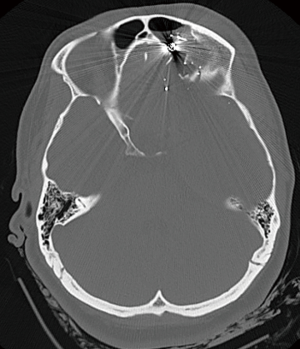

Traumatic parenchymal lesions

The parenchyma of the brain can be subject to injury and warrant surgical intervention as well. Indication for surgery in this type of injury is an intracerebral lesion with neurologic deterioration, and intracranial hypertension that is not responsive to medical management or signs of mass effect on CT (Figure 3). Furthermore, patients with a GCS less than 9 and a frontal or temporal lesion, with volume greater than 20 cc with midline shift greater than 5 mm, or cisternal compression or any lesion volume greater than 50 cc, may be considered for evacuation. Non-operative management can be considered when the parenchymal lesion causes no neurologic deficit, has no signs of mass effect and ICPs are controlled. The timing of proceeding to the OR should be emergent. Methods for surgical intervention depend on the location and nature of the injury. A craniotomy is generally recommended for any of these identified indications. If the patient is suffering from medically refractory intracranial hypertension, a bifrontal decompressive craniectomy (DC) may be considered. This will be reviewed in detail below. Other options for decompression include a temporal lobectomy, hemispheric DC and subtemporal decompression (41).